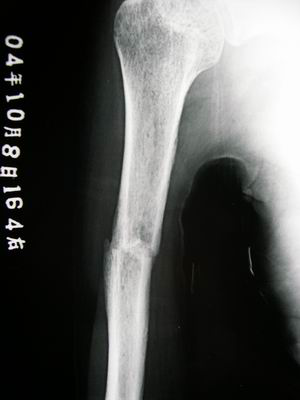

愈合了,但是强度还不够,骨的塑型和改建还没有完成呢